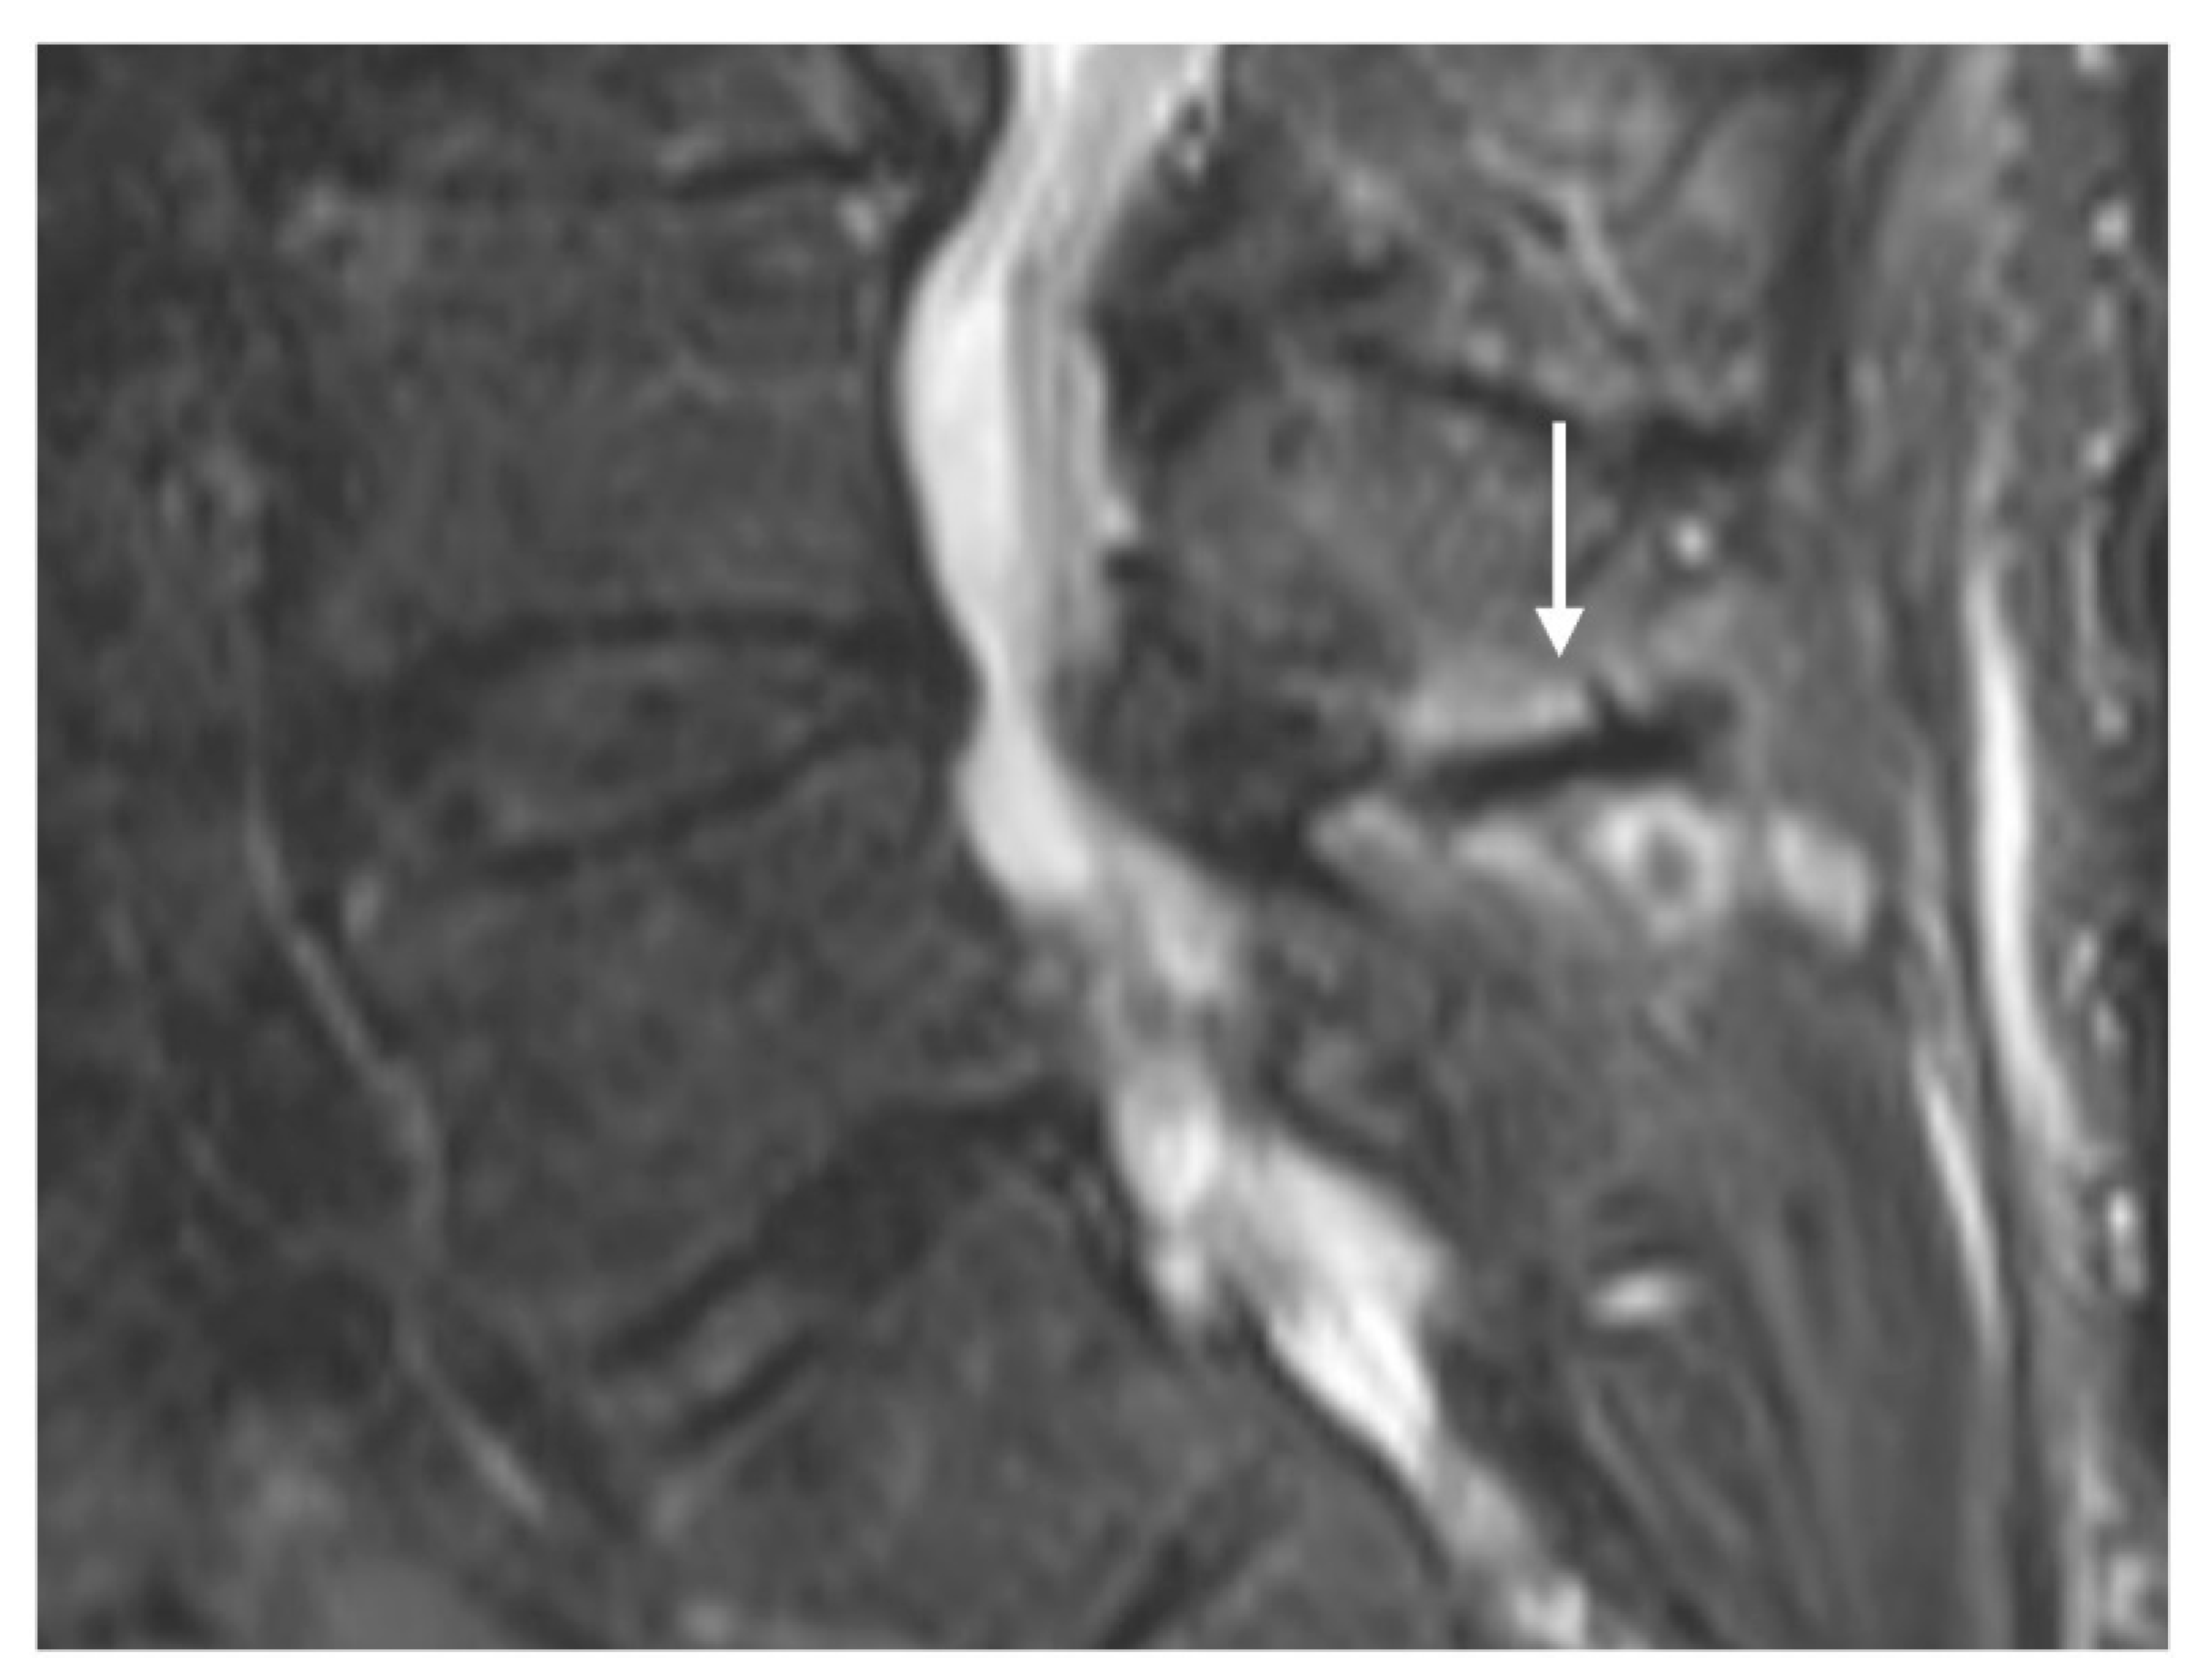

Characteristic imaging features include a close approximation of lumbar spinous processes (‘kissing spines”). CT may show reactive sclerosis, the resultant enlargement of the abutting spinous processes, and pseudoarthrosis formation. MRI can demonstrate interspinous bursal fluid as well as marrow oedema (Figure 1) [14]. Large bursal fluid collections can extend into the vertebral canal causing thecal sac compression.

Figure 1.

Sagittal STIR (short tau inversion recovery) image demonstrating Baastrup disease of lumber spinous processes (white arrow). Note the presence of reactive marrow oedema and sclerosis at the opposing surfaces of the spinous processes involved.